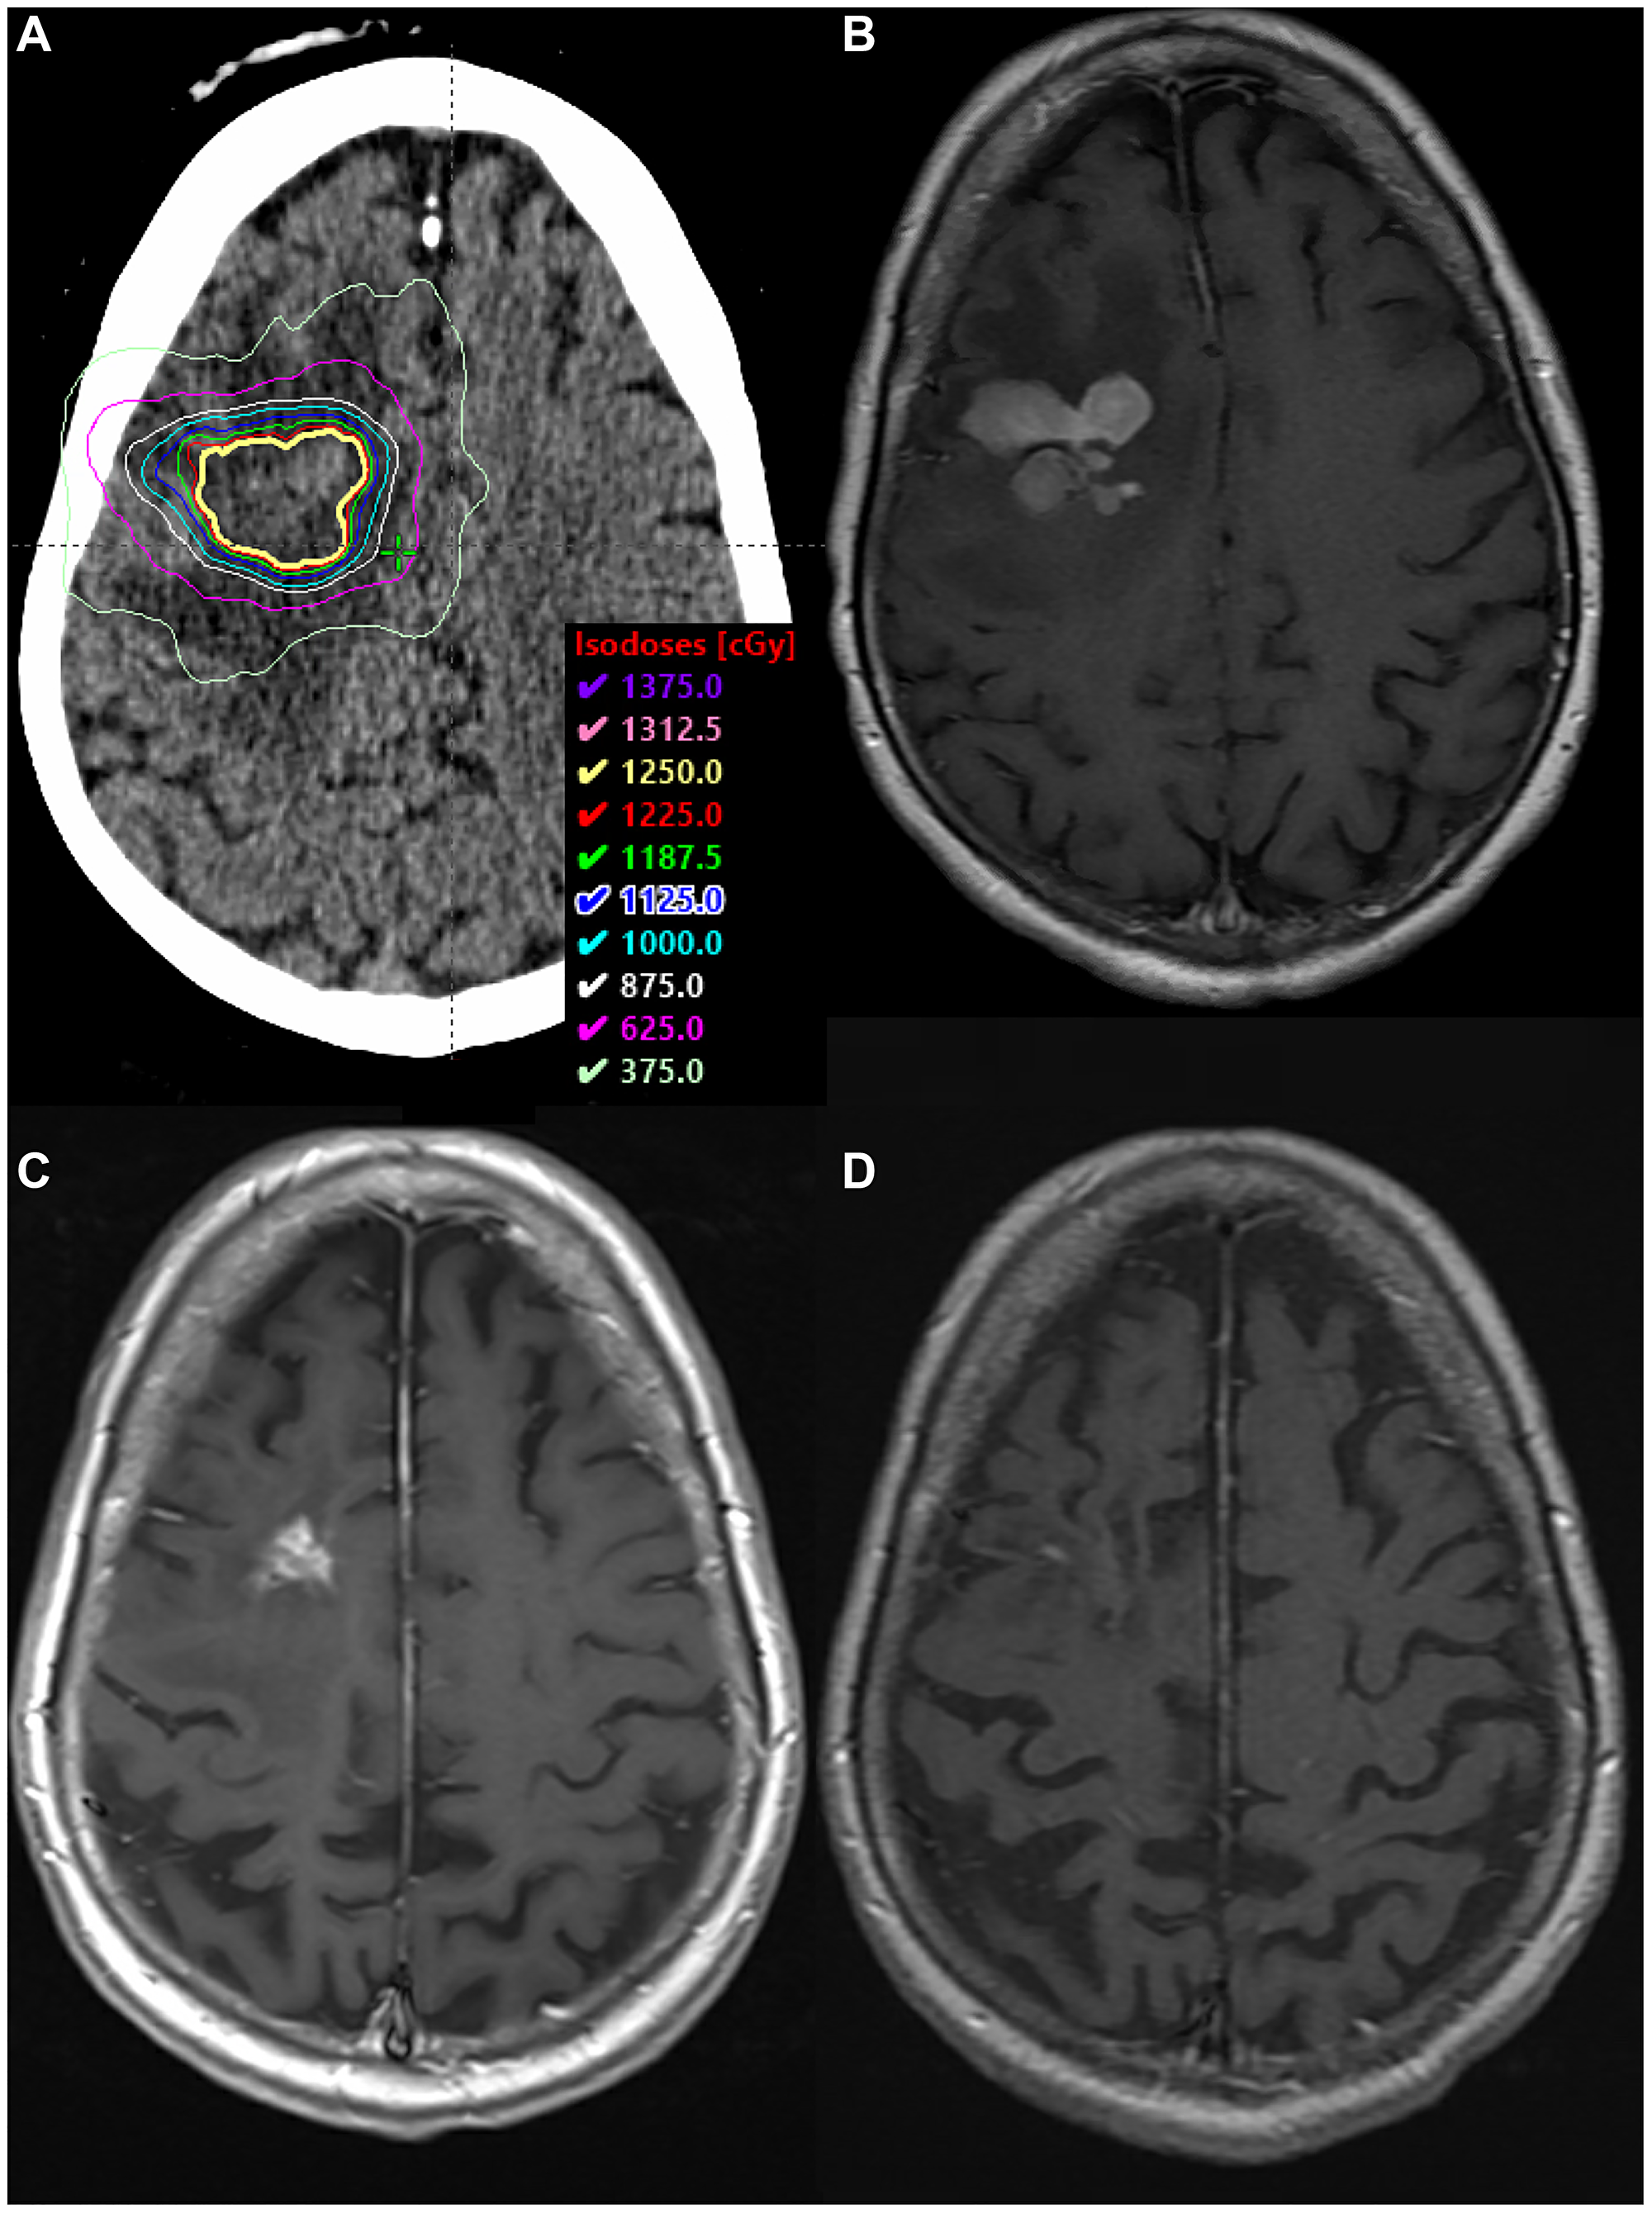

At the conclusion of treatment, MRI again revealed partial response with no reduction in the left frontal lesion. He received rd-WBRT with a 12.5 Gy SRS boost to the residual lesion in the left frontal lobe (Figure 3A and 3B). He then completed 10 cycles of consolidative TMZ 150 mg/m2 for 5 days in 28-day cycles. Intravitreal injections of MTX-R were added six months into the treatment.

SRS boost treatment plan and MRI scans

Figure 3: SRS boost treatment plan and MRI scans. (A) SRS boost treatment plan. (B) Enhancing residual disease prior to SRS boost on T1 FLAIR sequence with contrast. (C) Biopsy-proven RN along the left internal capsule, within the SRS boost volume, on T1 sequence with contrast. (D) MRI >2.5 years after BV, demonstrating complete radiographic response on T1 sequence with contrast.

Four months after initiating his intravitreal injections, MRI revealed a new enhancing nodule in the left anterior basal ganglia. This was presumed to be RN, and he was empirically started on pentoxifylline 400 mg three times daily and tocopherol 1000 units daily. Three months later, he presented with generalized seizures and MRI demonstrated a new 14-mm enhancing lesion along the left pre-central gyrus. Additionally, there was interval increase in the size of the previously seen left internal capsule lesion, with new central cavitation, increased T2 FLAIR hyperintensity suggesting vasogenic edema, and a 4-mm left-to-right midline shift (Figure 3C). He was started on high-dose steroids and levetiracetam. Biopsy revealed RN in the left internal capsule (Figure 2C) and recurrent DLBCL (CD45 99%, MGMT positive 99%) in the left motor strip (Figure 2D).

In the setting of recurrent disease, he completed another three months of MTX-R for 5 cycles followed by TMZ consolidation for 10 cycles. Given his biopsy-proven RN, he also received BV 7.5 mg/kg IV every 3 weeks for three total doses. BV was initiated after the fourth cycle of MTX-R. After two cycles of BV, MRI demonstrated a decrease in size and T2 hyperintensity at the location of his biopsy-proven RN. Both lesions continued to resolve on subsequent imaging, with stable T2 hyperintensity and complete loss of contrast enhancement (Figure 3D). Over two years later, he remains clinically and radiographically stable without seizures.